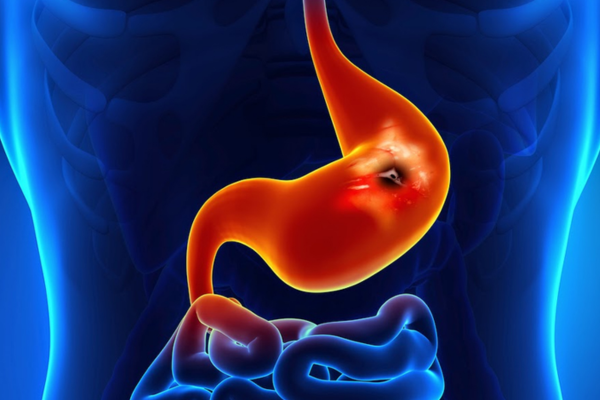

Upper and lower gastrointestinal bleeding can be life-threatening, presenting with vomiting blood, black stools, or severe weakness. It commonly occurs due to ulcers, tumors, or abnormal blood vessels.

Embolisation precisely blocks the bleeding vessel using catheters, controls bleeding rapidly, avoids emergency surgery, and stabilizes patients safely.